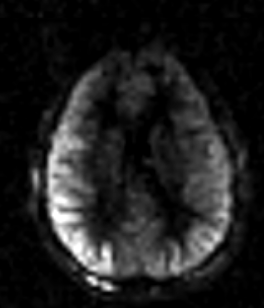

1.1 motion artifact

- Appearance: bright signal in the CSF, ventricles, or skull

- Cause: bulk/head motion

- Solution: fix the head with foam or tape